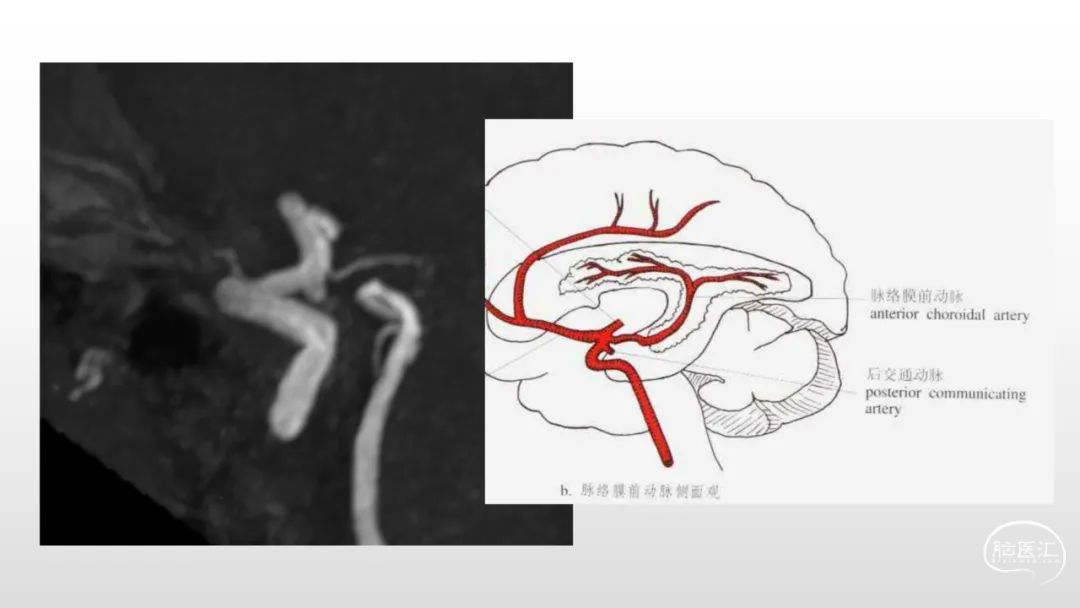

颅脑影像诊断基础知识讲座:《脑血管病》之出血、血管畸形、动脉炎及神经卡压